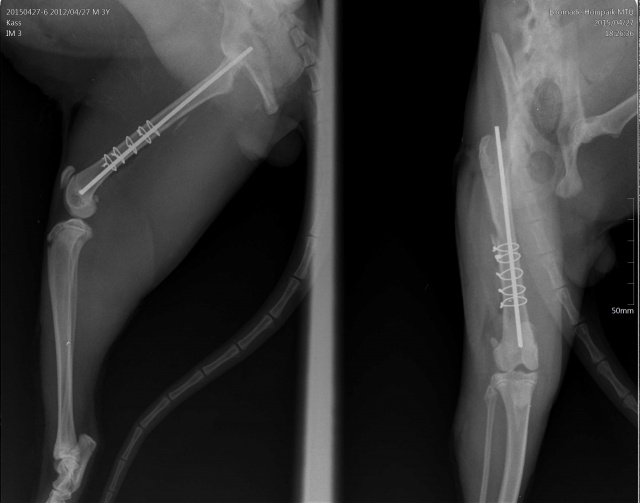

kiisu pareneb. Tal oli puusaluu murd (unustasin pildid lisada siia albumisse, kohe teen).

Praegu taastub ilusti operatsioonist. Keegi ei otsinud teda veel :(